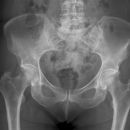

Beckenübersicht a.-p.

Fraktur, Luxation und degenerative Veränderungen (Coxarthrose)

Das Becken stellt sich vollständig, symmetrisch und gleichmäßig gut belichtet dar, einschließlich beider Hüftgelenke und der Trochanteren. Trochanter major darf den Schenkelhals nicht überlagern und der Trochanter minor ist gerade erkennbar.